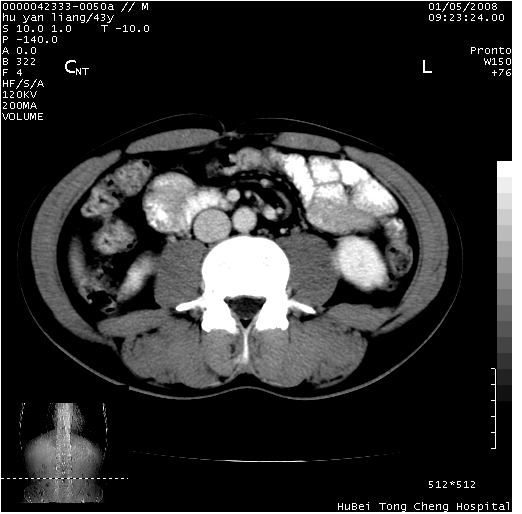

患者 男,43岁。右上腹不适1年余。既往有“肝右叶肝脓肿”病史,经保守治疗后痊愈。

b超提示:1)肝右叶肝内胆管结石。2)肝右叶占位性病变待排。

上中腹部ct轴位平扫+增强扫描(层厚10mm,螺距1.0,重建间隔10mm),图像如下:

肝右上叶偏后方较大团片状钙化灶,支持:肝脓肿后遗改变!

肝右叶钙化灶,考虑为肝脓肿后遗症。

肝右叶后段团块状钙化灶,结合病史考虑肝脓肿痊愈后表现。